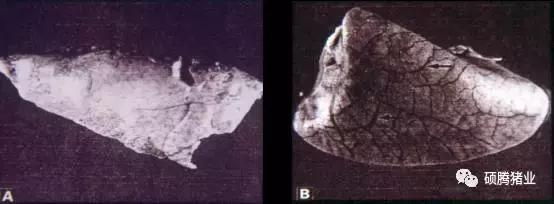

①黄曲霉毒素:黄曲霉毒素是黄曲霉和寄生曲霉产生的有毒代谢产物,是已知霉菌毒素中毒性最强、污染最普遍的一类毒素的总称。其分子量在312-346之间,化学结构是一个双氢呋喃和一个氧杂萘邻酮,依据化学结构和产生衍生物的不同可分为B1、B2、G1、G2、M1、M2等20余种,污染饲料的主要是B1、B2、G1、G2 4种。它具有耐热特点,其熔点200-300℃,裂解温度280℃,难溶于水,易溶于有机溶剂和油脂。黄曲霉毒素的中毒症状主要表现在:损害肝脏(图1)、胃肠功能障碍、生殖能力下降、饲料利用率降低、贫血和黄疸(图2)、免疫系统受损、癌症。

图1 在相同时间内给予逐渐增高剂量的黄曲霉毒素后豚鼠肝脏的眼观病理变化(John等,2003)